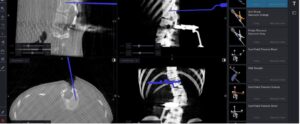

Spine surgery requires exceptional precision. Every millimeter matters because the spinal cord is the main communication pathway between the brain and the entire body. Any

In recent years, spine surgery has seen significant advancements, thanks to the integration of cutting-edge technologies. One of the most impactful innovations is O-arm guided

Spine surgery has evolved dramatically over the past few decades, moving from traditional open techniques to minimally invasive procedures that prioritize patient safety, precision, and